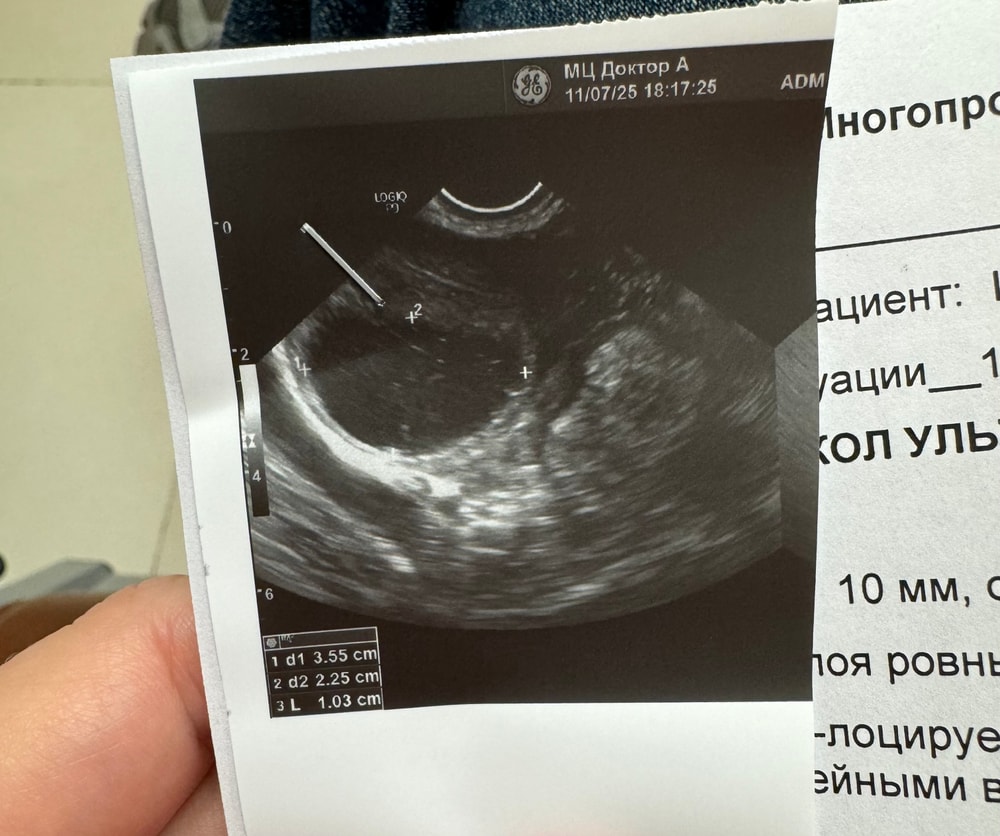

Добрый день, после укола ХГЧ 10 000 ед. сходила на узи через 6 дней, сказали киста, очень больно двигаться, почти все время колющие ощущения, девчонки миленькие подскажите это киста ЖТ или обычная, были ли у кого такие ощущения?

ниже прикрепляю узи